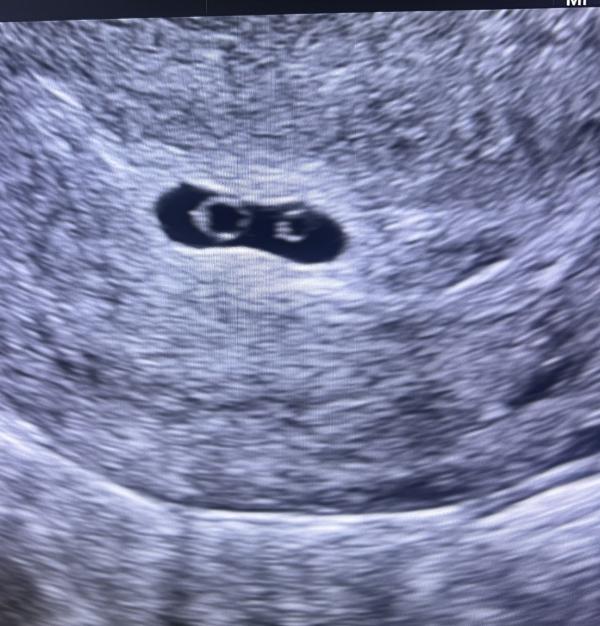

Сегодня на приём пришла девушка. Дома 4-ро деток. Однополых. Тест положительный. Спрашиваю , будет ли сохранять беременность, отвечает , что только, если там будет сердцебиения. Ставлю датчик, а там..там два колечка 🥹 монохориальная двойня ❤️❤️. Сердцебиения пока ещё нет..девушка была в шоке. Говорит пока ехала в клинику, были мысли «а вдруг там двое, как потом убрать»…